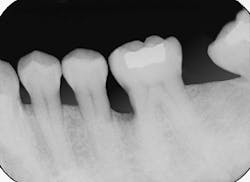

Figure 1 is a radiograph of a 38-year-old nonsmoking female in good health. Vertical bone loss is evident on the mesial aspect of tooth #19. The defect appears deep and the base extends toward the apical one third of the root. Clinical examination revealed 8mm probing depths at the mesiobuccal and mesiolingual line angles. A three-wall defect was diagnosed.

Figure 1: A periapical radiograph indicates angular bone loss on the mesial aspect of tooth #19.